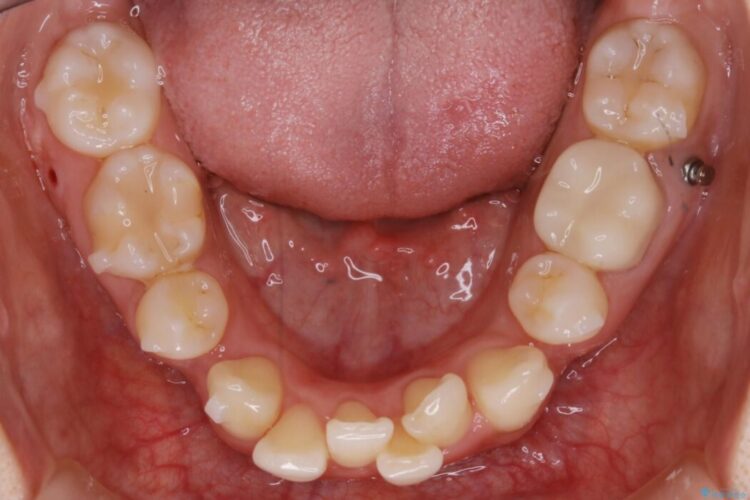

まず噛み合わせに問題が少ない奥歯の位置を極力変えないように上下左右4番目の歯を抜歯することで歯列矯正のためのスペースを確保し、空いた隙間で前歯の凹凸をきれいに並べていくこととしました。

笑った時に見えるガタついていた見栄えが改善されて歯列弓もきれいな形に整い、患者様にはご満足いただけました。